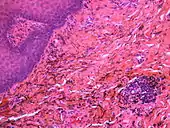

| Amalgam tattoo in upper labial sulcus in an edentulous individual, left behind after teeth have been lost/extracted | |

Amalgam tattoo usually occurs on the mandibular gingiva, often in an area in which an apicoectomy ("root-end filling") with amalgam was carried out.[3]: 138 After the gingiva, the alveolar mucosa and the buccal mucosa are the next most common sites, although any mucosal site in the mouth is possible.[1] It is painless, and appears as a blue-black or grey discolored macule on the surface of the mucosa.[3]: 138 [4]: 330 [5]: 183 The borders of the tattoo are variable, and may be well defined, irregular or diffuse.[1]